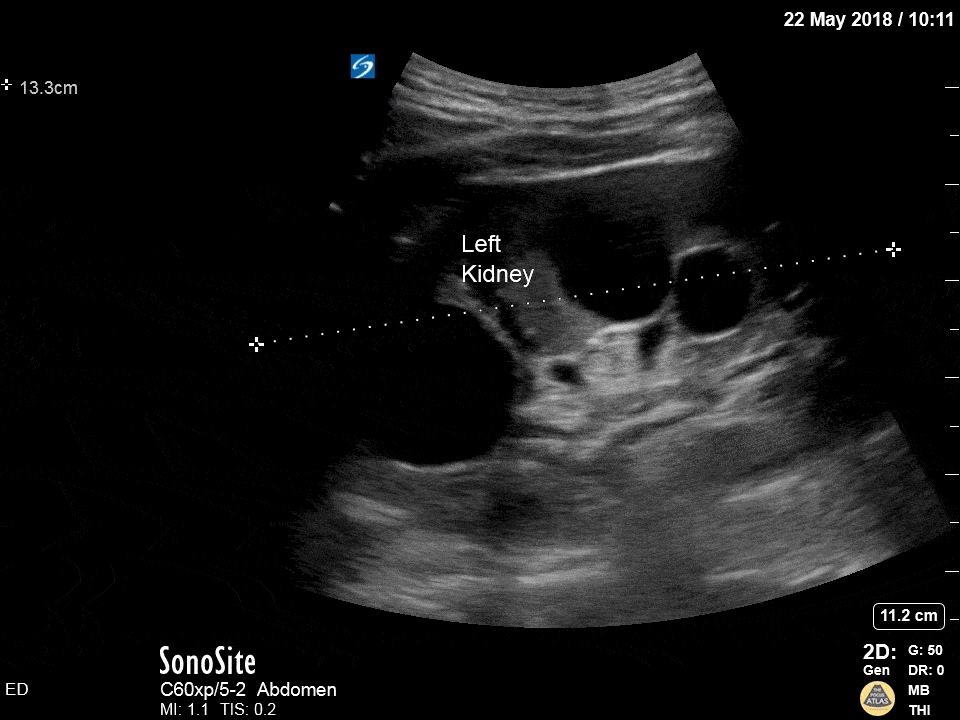

Hydronephrosis, right? Wrong! These are polycystic kidneys! Differentiate the two by looking for communication with the collecting system. Dr. Michael Trauer